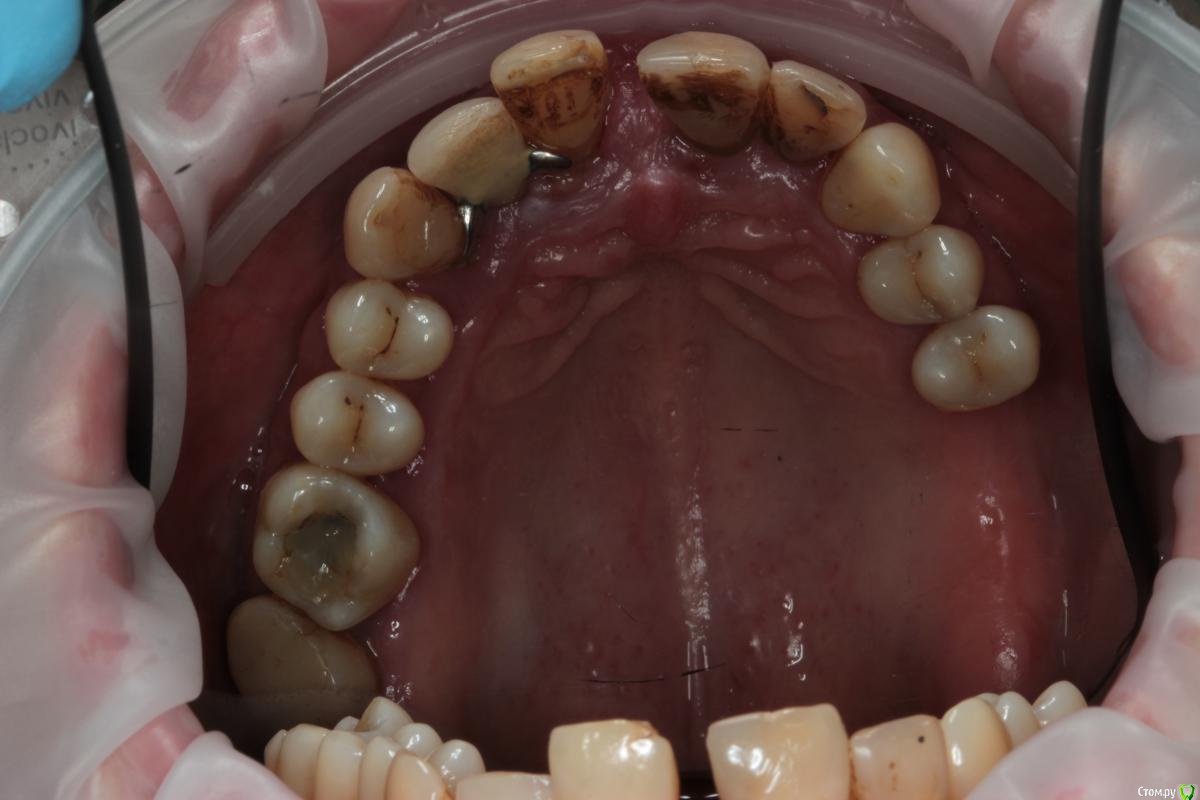

Abuk Опубликовано 27 ноября, 2015 Поделиться Опубликовано 27 ноября, 2015 (изменено) 1.bmp2.bmp3.bmp4.bmpЛечение.Альгинатные слепки,восковая моделировка.Удаление зубов и имплантата,удаление грануляций.Установка имплантатов,заполнение лунок графтом.сст,Времяхи по ключу. Изменено 27 ноября, 2015 пользователем Abuk 13 Ссылка на комментарий

bullbull Опубликовано 30 ноября, 2015 Поделиться Опубликовано 30 ноября, 2015 А что за винтик-красавЕц на 5-й фоточке? Ссылка на комментарий

Abuk Опубликовано 30 ноября, 2015 Автор Поделиться Опубликовано 30 ноября, 2015 А что за винтик-красавЕц на 5-й фоточке?Честно не знаю, лет пять назад ставила). Еще и кламера сделали на коронке. Столько смеялся когда увидел) Ссылка на комментарий